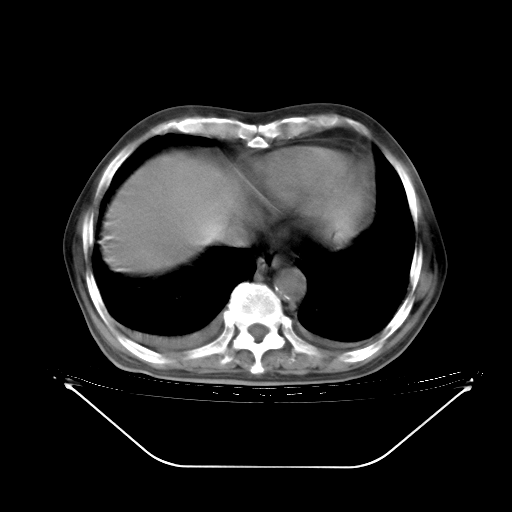

胸腹部CT,诊断意见:左上肺叶钙化灶、左侧胸膜局限性增厚并钙化、胆囊炎。描述部分肺组织呈磨玻璃样改变。

今天复查肺部CT,发现双肺广泛磨玻璃样改变。所以我把3月19日和5月9日相隔50天的肺部CT上传。请大家会诊。

5月9日肺部CT(在4月27日齐鲁医院肺部CT描述部分肺组织磨玻璃样改变,12天后肺组织广泛磨玻璃样改变)

大致读了系列胸部CT:纵隔窗无明显异常,肺窗:从4、27至今:主要是双肺中下野外带可见毛玻璃样改变,目前处于急性肺泡炎阶段,至于原因考虑1、结替组织或胶原血管性疾病所致?2、恶性疾病如恶组在肺部所致的表现或细支气管肺泡癌?3、药物或其它原因如肺蛋白沉着症所致肺泡炎目前不太可能?总之,明天就去请我院的呼吸科、感染科、血液科和临免专家会诊哈。